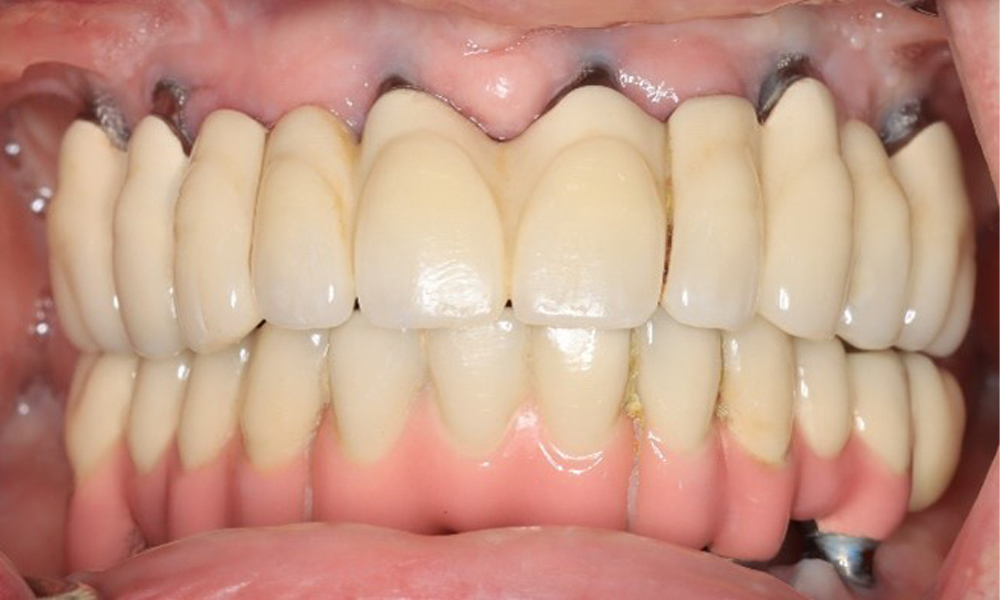

74-годишен пациент се явява за консултация. Анамнезата показва, че пациентът има добре контролирана хипертония и приема Lixiana. Освен това пациентът е имал карцином на бъбрека през 2020 г. Начинът на живот на пациента е без забележки. Няма останали естествени зъби и има шест импланта в горната и долната челюст, на които са поставени коронки или мостове. Текущите данни не показват периимплантатен мукозит или периимплантит, но въпреки това периодично има (незначително) кръвене при имплантите (възстановяванията).

Възстановявания: импланти в области 011, 013, 015, 021, 023, 025, 031, 033, 035, 042, 044, 046

При този пациент от съществено значение са мотивацията и инструкциите по отношение на оралната хигиена. Правилната грижа за имплантите е особено важна. Добрата домашна орална хигиена играе важна роля за дългосрочното стабилизиране на здравето на устната кухина и имплантите.

При инструментализирането на импланти се изисква специален подход. Изборът на подходящи пудри и инструменти е от решаващо значение за запазване на повърхността на импланта, като същевременно се гарантира ефективно почистване. Това включва целенасочено използване на устройства за полиране със специални перио накрайници. Изборът на подходяща пудра може да се коригира въз основа на нуждите и рисковете, като например се вземат предвид нивата на абразивност и диетата (напр. без захар, с ниско съдържание на сол).

Понастоящем състоянието на периимплантатите е стабилно. Поради сложността на надстройките пациентът има умерен риск от развитие и нисък риск от прогресия на периимплантни заболявания.